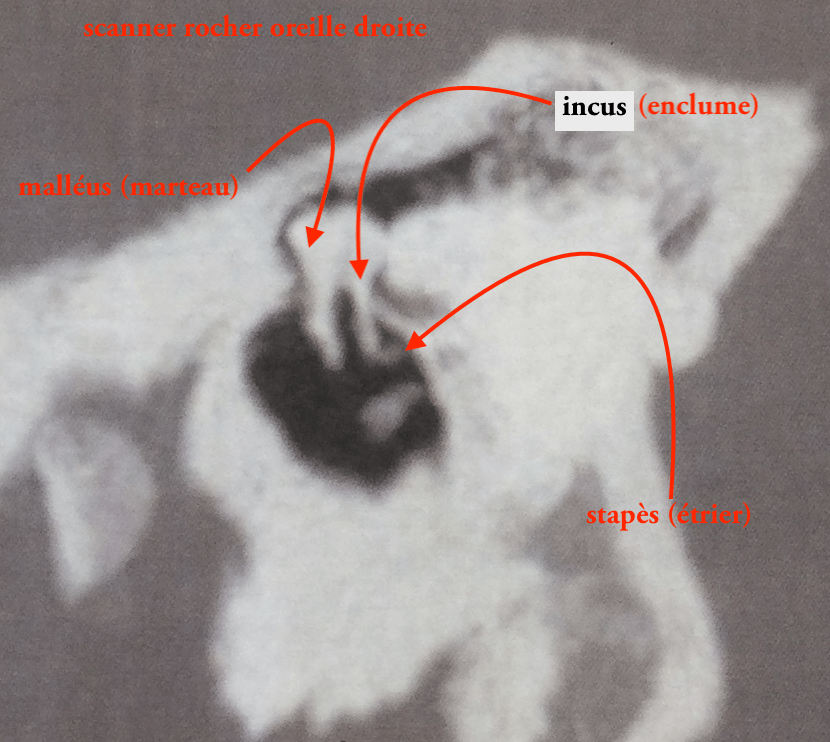

Hors-sujet quelques images de scanner pour comprendre l'articulation des 3 osselets avec l'ancienne et "nouvelle" dénomination selon la Terminologie anatomique de 1998, révisée en 2005 (dont il n'y a toujours pas de traduction française..): le malleus (que j'ai francisé en malléus, marteau), l'incus (et non uncus!, enclume) et enfin le stapes (pareil j'ai francisé en stapès, parfois écrit stapés, étrier).